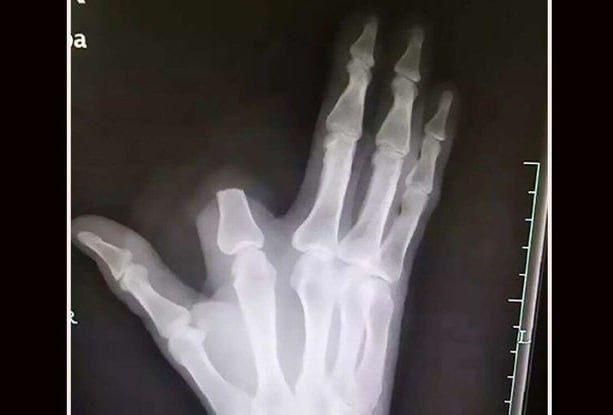

История произошла в Китае: 60-летний фермер из провинции Чжэцзян, работая в поле, запаниковал после укуса и ампутировал себе указательный палец подручными средствами.Он перевязал руку и сам добрался до больницы, где врачи сообщили, что опасности...